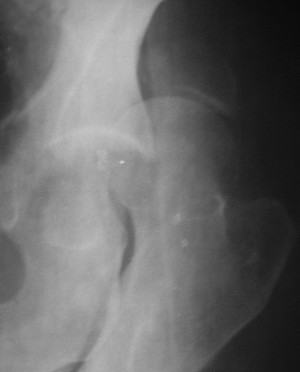

Контрольный снимок перед разрешением нагрузки прямой 13/10/03

|

Два месяца нагрузки без костылей 19/12/03

Еще месяц 20/02/04

Больной 18 мая 2003 года в автоаварии получил перелом левой вертлужной впадины, вывих бедра. Госпитализирован в один из стационаров области.Вывих вправлен. В последствии бедро вывихивалось еще дважды. На консультацию был представлен снимок от 19.05.03г., больной переведен к нам 3.06.03г. Снимок при поступлении - перелом впадины, задне-верхний вывих бедра. 05.06.2003 г. выполнено открытое вправление вывиха левого бедра и остеосинтез стенки вертлужной впадины двумя винтами. Послеоперационный период без осложнений. Объем движений в левом тазобедренном суставе восстановился полностью. Выписан на амбулаторное лечение в удовлетворительном состоянии с рекомендациями 3 месяца ходить на костылях без нагрузки на оперированную конечность. На контрольных рентгенограммах левого тазобедренного сустава 13.10.2003 г. - признаки консолидации перелома; плотность, форма головки и состояние суставных поверхностей удовлетворительные. Разрешена дозированная осевая нагрузка, на конечность с использованием дополнительной опоры. 19.12.2003 г. больной обратился с жалобами на боли в левом тазобедренном суставе. На рентгенограммах левого тазобедренного сустава 19.12.2003 г., 20.02.04г. - асептичекий некроз головки бедра. 5.04.04г. - эндопротез. Сейчас ходит без трости, не хромает. Особенность эндопротезирования - при удалении винтов прослежена линия перелома заднего края впадины и предложено установить чашку несколько меньшего диаметра, чтобы она была покрыта несломанной частью.